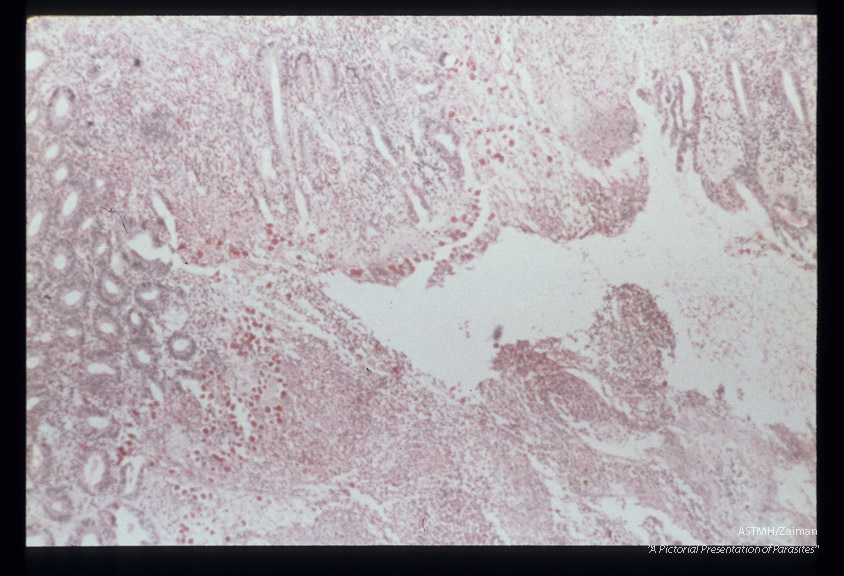

Best carmine stained section of rectum.

Entamoeba histolytica

Description: Best carmine stained section of rectum.